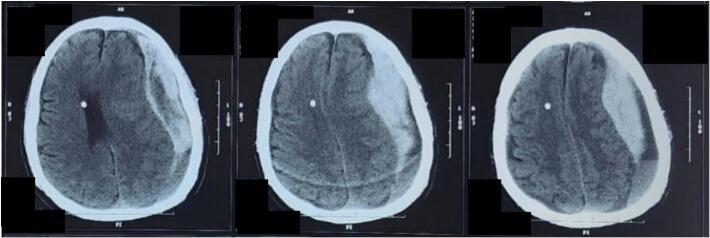

CASE PRESENTATION

A 74-year-old man with comorbid diabetes mellitus and hypertension presented with decreased consciousness (Glasgow Coma Scale (GCS) 4; E1M2V1) with stable hemodynamics. Isochoric pupils and right motoric lateralization were found upon neurological examination. CT scan of the brain without contrast showed acute and chronic SDH in the left frontotemporoparietal area with a midline shift 2 cm to the right. An evacuation craniectomy of the SDH was performed. Postoperative care included mechanical ventilation, monitoring, fluid balance maintenance, and medication. The patient showed improvement during follow-up and was weaned off mechanical ventilation on the 5th day after surgery.

一名74岁患有糖尿病和高血压合并症的男性患者,意识下降(格拉斯哥昏迷量表(GCS)4分;E1M2V1),血流动力学稳定。神经系统检查发现双侧瞳孔等大,右侧有运动性偏侧化。脑部未增强CT扫描显示左额颞顶叶区域有急性和慢性SDH,中线向右移位2厘米。对SDH进行了颅骨切开引流术。术后护理包括机械通气、监测、维持液体平衡和药物治疗。患者在随访期间病情好转,术后第5天脱机。